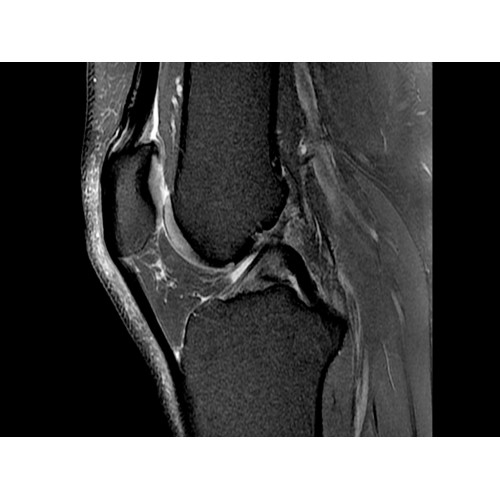

• РЧ-катушки, оптимизированные для исследования конкретных участков тела — элементы катушек высокой плотности располагаются вокруг исследуемых участков тела и при необходимости обеспечивают расширенный охват и оптимальное качество изображений при каждой процедуре.

• Широкое поле зрения — поле зрения шириной 50 см позволяет охватывать крупные анатомические области за меньшее число сканов.